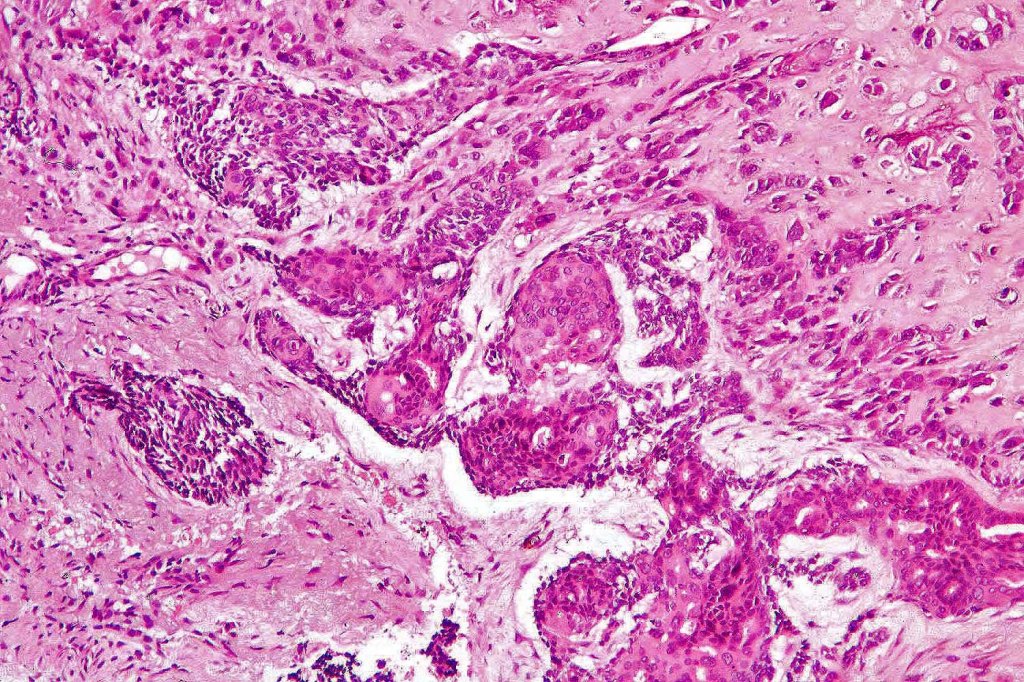

Carcinosarcoma

Cutaneous carcinosarcoma (metaplastic carcinoma, carcinoma with heterologous differentiation)

Histological features

•Osteoid

•Chondroid

•Smooth muscle

•MFH-like features with osteoclasts

•Neural differentiation